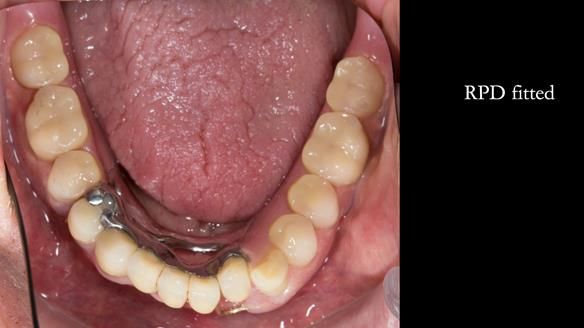

Instead, we made a Scandinavian-style, metal-based lower RPD.

It was made promptly, then relined gradually over the following year

to optimise fit, comfort, and support.

It’s worth saying that the lower denture in this case was made in the early days of Rowan and me using the Scandinavian approach. Rowan cast the metalwork himself for this denture.

Looking back, we would make this denture more hygienic now. The design and finish would be more refined and delicate, particularly when compared with the upper metalwork, which was made later using Chris Hesketh’s chrome work. I will discuss this in detail at the study club.

That said, the lower denture worked beautifully. It did exactly what it was meant to do, even though, by today’s standards, it looks a little agricultural.